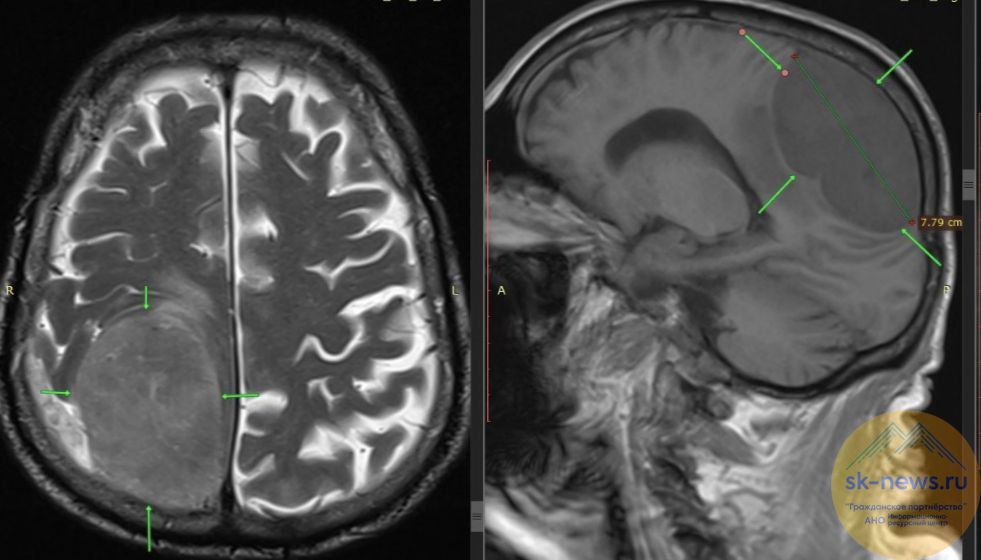

Когда мужчину доставили в больницу, состояние напоминало инсульт — не работали левая нога и вся левая сторона тела. Однако экстренное обследование показало истинную причину: в правой теменно-затылочной области мозга, которая отвечает за движение противоположной половины тела, находилась гигантская опухоль размером 8×7 сантиметров.

Нейрохирурги провели сложнейшую операцию — костно-пластическую трепанацию черепа и полностью удалили новообразование.

Контрольное обследование показало, что операция прошла успешно: мозг расправился, кровотечений нет, а движения в левой половине тела у пациента восстановились.